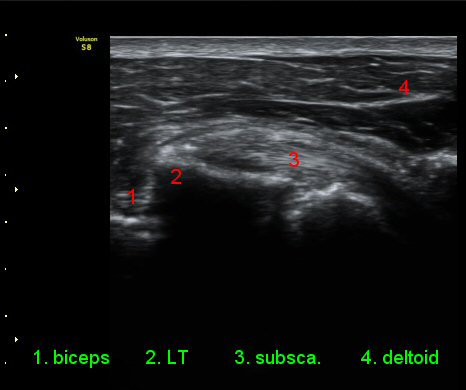

ŽÃÊÀÚ¸¦ ¾à°£ ´Ù¸®ÂÊ, ³»ÃøÀ¸·Î À̵¿ÇÏ´Ï °ß°©ÇÏ±Ù°Ç Ç¥Ãþ¿¡ ¸¹Àº ¾çÀÇ ¼ö¾×Àú·ù°¡ °üÂûµÈ´Ù(»çÁø 3).